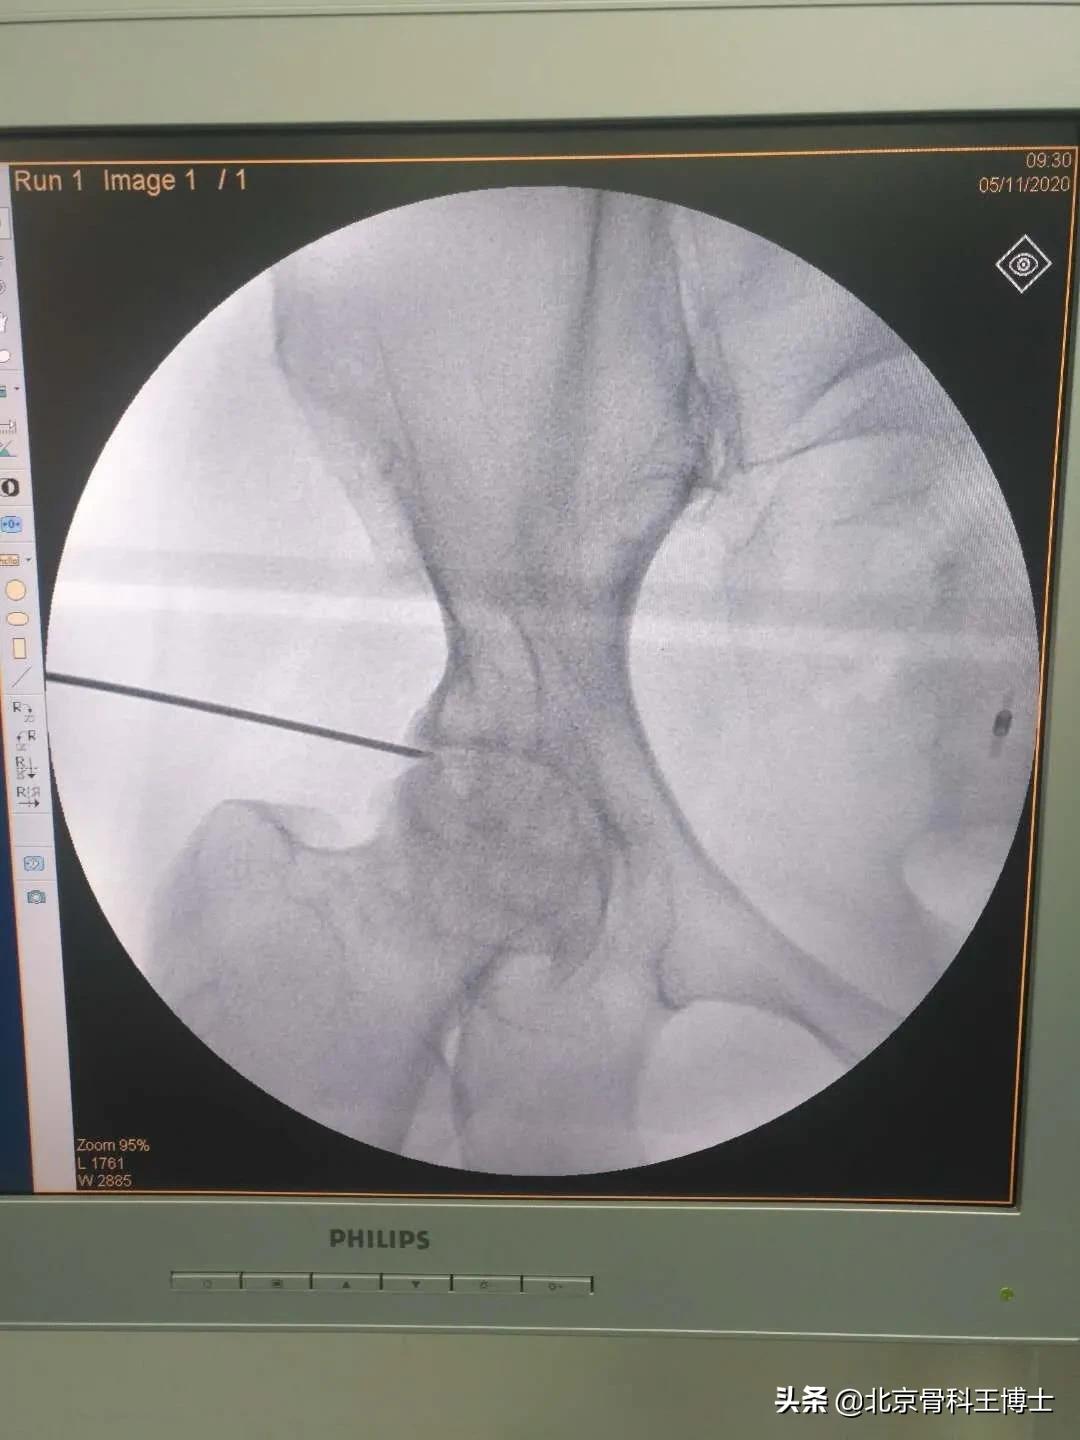

我研发的细胞移植治疗股骨头坏死保髋治疗,已经完成3500余例病人。有很多病人手术后已经超过10年。他们至今依然在各个行业从事着工作。有的病人甚至还从事着重体力劳动。大量的临床实践证明,股骨头坏死是完全能够治愈的。

细胞移植治疗股骨头坏死这种方法特别适合于年轻病人,尤其是因饮酒或激素引起的股骨头坏死。我们总结1万余例病人,得出的结论是,30~40岁的年轻病人患病率最高。